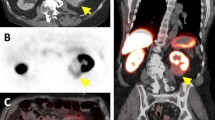

In the orthotopic UMRC3 lung tumor model, PET/CT imaging did not provide enough contrast to allow discrimination of tumors from normal tissue (Fig. 5b). Instead, a 7 T Bruker MR equipped with a Cubresa NuPETTM insert (PET/MRI system) provided superior visualization of the orthotopic lung tumor model. UMRC3 lung tumor-bearing mice were imaged dynamically for 1 h to identify the imaging timepoint with the lowest non-specific uptake. In the MR images, the tumor could be clearly discriminated from normal tissue (Figs. 5a, 3a, and d). In contrast, it was difficult to distinguish tumor from normal tissue such as the heart with CT (Fig. 5b). Tracer uptake was measured in the heart, contralateral lung, tumor, bones, and muscle and reported as %ID/cc. TACs showed higher uptake of [18F]FGln in the tumor compared to muscle or contralateral lung at each time point (Fig. 5e). T/M decreased over time from 3 to 2 (Fig. 5d). Based on these TACs, 40 min post-injection was identified as the optimal imaging time point. A similar optimum time window for tumor uptake and blood clearance has been observed in other [18F]FGln animal experiments [18]. Because tumor engraftment was often observed in both lungs of UMRC3 tumor-bearing mice, tumor-to-contralateral lung ratios did not accurately reflect the uptake of the tracer compared to healthy tissue. To better understand the tumor-to-healthy lung ratio, uptake of [18F]FGln in the lung of tumor-bearing mice was compared with uptake in the lung of healthy mice. This comparison was done by placing the tumor VOI from each tumor-bearing mouse into the left lung of a set of 5 healthy, non-tumor-bearing mice. Uptake of the tracer in the healthy lung was measured for each mouse and averaged to give a unique control for each tumor-bearing mouse. These measurements are labeled as control in Fig. 5e and were used to calculate tumor-to-control (T/C) ratios. Individual measurements taken from each tumor-bearing mouse 20 and 40 min post-tracer injection are shown in Fig. 5e. We observed a median T/M of approximately 2 and T/C of approximately 1.5, validating the usefulness of [18F]FGln-PET/MRI to assess renal cell carcinoma lung lesions.

Quantification of [18F]FGln uptake in UMRC3 lung tumor-bearing mice and healthy control mice by PET/MR. (a) Representative [18F]FGln static PET image overlaid on a MR image of a UMRC3 tumor-bearing mouse. Areas depicting where VOIs of tumor (T), muscle (M), heart (H), and contralateral lung (CL) were drawn are labeled. Tumor VOI is shown by a white dotted line. (b) Representative [18F]FGln static PET image overlaid on a CT image of a UMRC3 tumor-bearing mouse. It was impossible to distinguish tumor from heart due to the poor soft tissue contrast of the CT image. (c) Time-activity curve showed the average uptake of the tracer in the tumor, contralateral lung, muscle, bone, and heart of the UMRC3 tumor-bearing mouse in Fig. 5a expressed as %ID/cc. Error bars represent the standard deviation within each VOI. (d) Tumor-to-muscle ratios (T/M) observed in the UMRC3 tumor-bearing mouse in Fig. 5a over time. Error bars represent the standard deviation within each VOI. (e) Plot of tracer uptake in %ID/cc in the lung of tumor-bearing mice (Tumor) and healthy mice (Control) measured 20 min (red) and 40 min (blue) post-injection. T/M of tumor-bearing mice and tumor-to-control mouse lung ratio (T/Control) are also shown in %ID/cc. Each data point represents an individual mouse; colored columns represent the average; error bars represent the standard deviation of the mean

We initially sought to visualize UMRC3-lung lesions by PET/CT, but CT could not provide enough contrast in the model to distinguish tumor from healthy tissues. Using PET/MRI, we were able to easily visualize the lung lesions by MRI and register the PET image to the MR image. [18F]FGln PET provided visualization of UMRC3 lung lesions at 20 to 40 min post-tracer injection with a tumor-to-muscle ratio of approximately 2 and tumor-to-healthy lung ratio of 1.5. The high metastatic nature of this cell line prevented the use of the contralateral lung as a control. However, using the lung of healthy mice as a control provided a rigorous and unbiased quantification of [18F]FGln uptake.